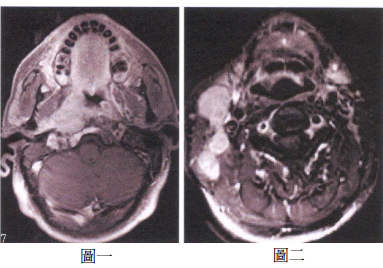

74 51 歲男性,無意間摸到右側頸部腫瘤。根據 MRI 之注射 Gd-DTPA 後的 T1WI with fat-suppression 影 像(如圖一、圖二),最可能的診斷是:

(A) Tongue carcinoma with neck metastatic lymphadenopathies (B) Buccal mucosal carcinoma with neck metastatic lymphadenopathies (C) Minor salivary adenocarcinoma with neck metastatic lymphadenopathies (D) NPC with neck metastatic lymphadenopathies